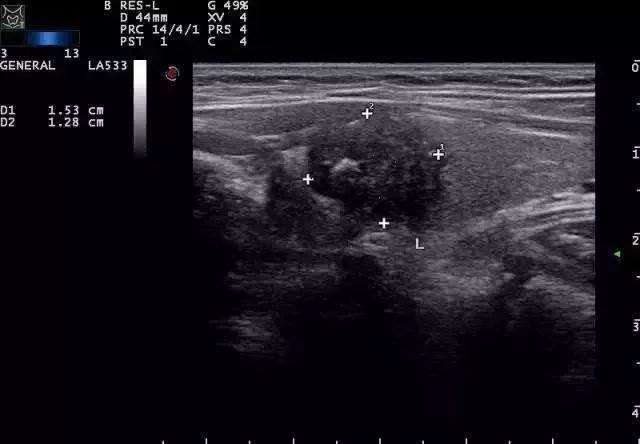

绝大部分甲状腺结节是良性病变,仅5%-15%为恶性,即甲状腺癌,因此良恶性鉴别是甲状腺结节的评估要点,首选方法是进行甲状腺和颈部淋巴结超声检查。其中,提示结节有恶性可能的超声征象特点如下:

(1)实性低回声结节;

(2)结节内血供丰富紊乱(TSH正常情况下);

(3)结节形态和边缘不规则、晕圈缺如,纵横比>1;

(4)微小钙化、针尖样弥漫分布或簇状分布的钙化;

(5)颈部淋巴结异常影像,如淋巴结呈圆形、边界不规则或模糊,内部回声不均、内部出现钙化、皮髓质分界不清、淋巴门消失或囊性变等。